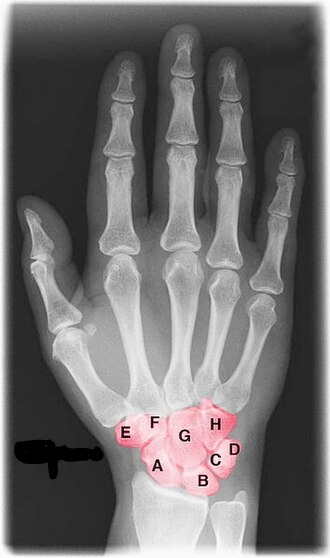

What is this region?

Carpal

How many bones does one hand and wrist have? Why is that necessary?

One hand and wrist has 27 bones, which is essential for a wide range of motion and the ability to perform fine motor skills